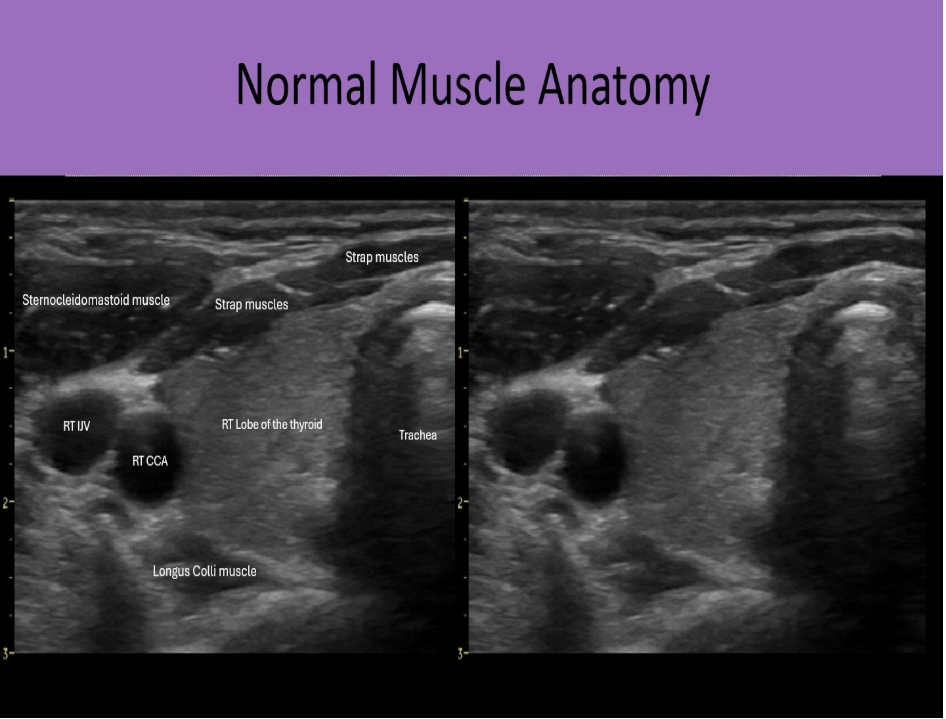

Which muscle group is located posterior to the thyroid gland?

C. longus colli muscle

Strap muscles are anteromedial to the gland. Sternocleidomastoid muscles are anterolateral to the gland. Longus Colli muscles are posterior to the thyroid lobes.

Find the sternocleidomastoid muscle

The sternocleidomastoid muscles are anterolateral to the thyroid gland

Which muscle group is located anteromedial to the lobes of the thyroid gland?

C. strap muscles